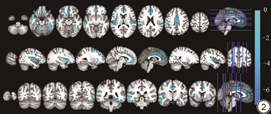

与放疗前相比,NPC患者在放疗后,颞叶(双侧梭状回、右侧颞上回、右侧颞中回、右侧颞下回)、枕叶(左侧舌回、右侧矩状回)、额叶(左侧眶部额中回、左侧眶部额下回)、边缘叶(左侧岛叶、双侧前扣带回)、灰质体积仍显著减小,同时出现右侧岛叶,左侧颞叶、双侧额上回、右侧眶部额下回、右侧小脑、右侧海马旁回灰质体积减小(cluster水平FWE校正,P<0.001)(图2、表2)。

放疗后与放疗前相比灰质体积减小的脑区

Brain regions with reduced gray matter volume after radiotherapy compared to before radiotherapy